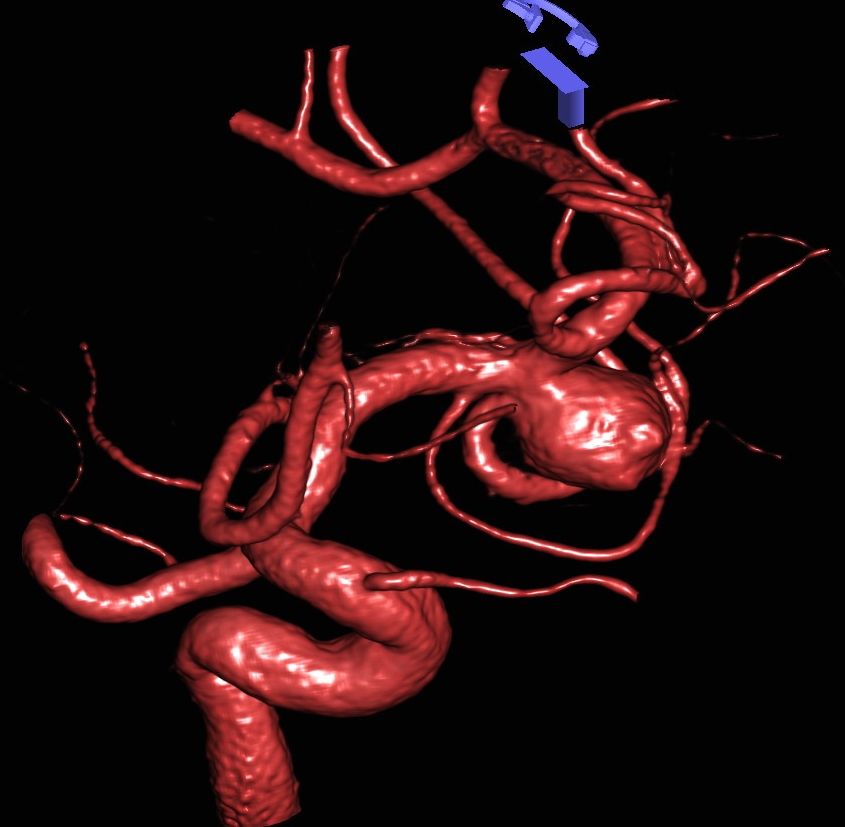

3D Darstellung eines Aneurysmas

CT Angiographie eines Aneurysmas

CT Angiographie eines Aneurysmas vor und nach mikrochirurgischem Clipping

Bei Aneurysmen handelt es sich um Gefäßaussackungen, die hauptsächlich an der Aufzweigung von Blutgefäßen auftreten. Man unterscheidet sackförmige (sakkuläre), welche die häufigste Form darstellen, von unregelmäßigen (fusiforme) Aneurysmen. Die Größe der Aneurysmen variiert von einigen Millimetern bis zu mehreren Zentimetern. Ist ein Aneurysma größer als 25mm, spricht man von Riesenaneurysmen.

Als schnellste und sicherste Maßnahme gilt das craniale Computertomogramm (CCT). Hier lässt sich eine frische SAB meist zuverlässig darstellen, wobei auch bereits richtungsweisende Befunde, wie das Ausmaß der Blutung und eine eventuelle Lokalisation eines möglichen Aneurysmas bestimmt werden können. Darüber hinaus kann ein Angio-CCT, bei dem zusätzlich Kontrastmittel verabreicht wird und dann die intrazerebralen Blutgefäße gesondert rekonstruiert und dargestellt werden, weitere Informationen liefern. Der sogenannte “Goldstandard” zur Diagnose zerebraler Gefäßmissbildungen ist jedoch die zerebrale Angiographie. Dabei wird mit Hilfe eines speziellen Katheters über die Leisten- oder Armarterie Kontrastmittel gegeben und die zerebralen Blutgefäße hoch selektiv dargestellt. Sollten sich auf dem initialen CCT Zeichen des Hirnwasseraufstaus zeigen, der durch ein Verstopfen der Abflusskanäle durch das neu aufgetretene Blut bedingt ist, ist oft die Anlage einer Hirnwasserableitung nach außen notwendig (externe Ventrikeldrainage).